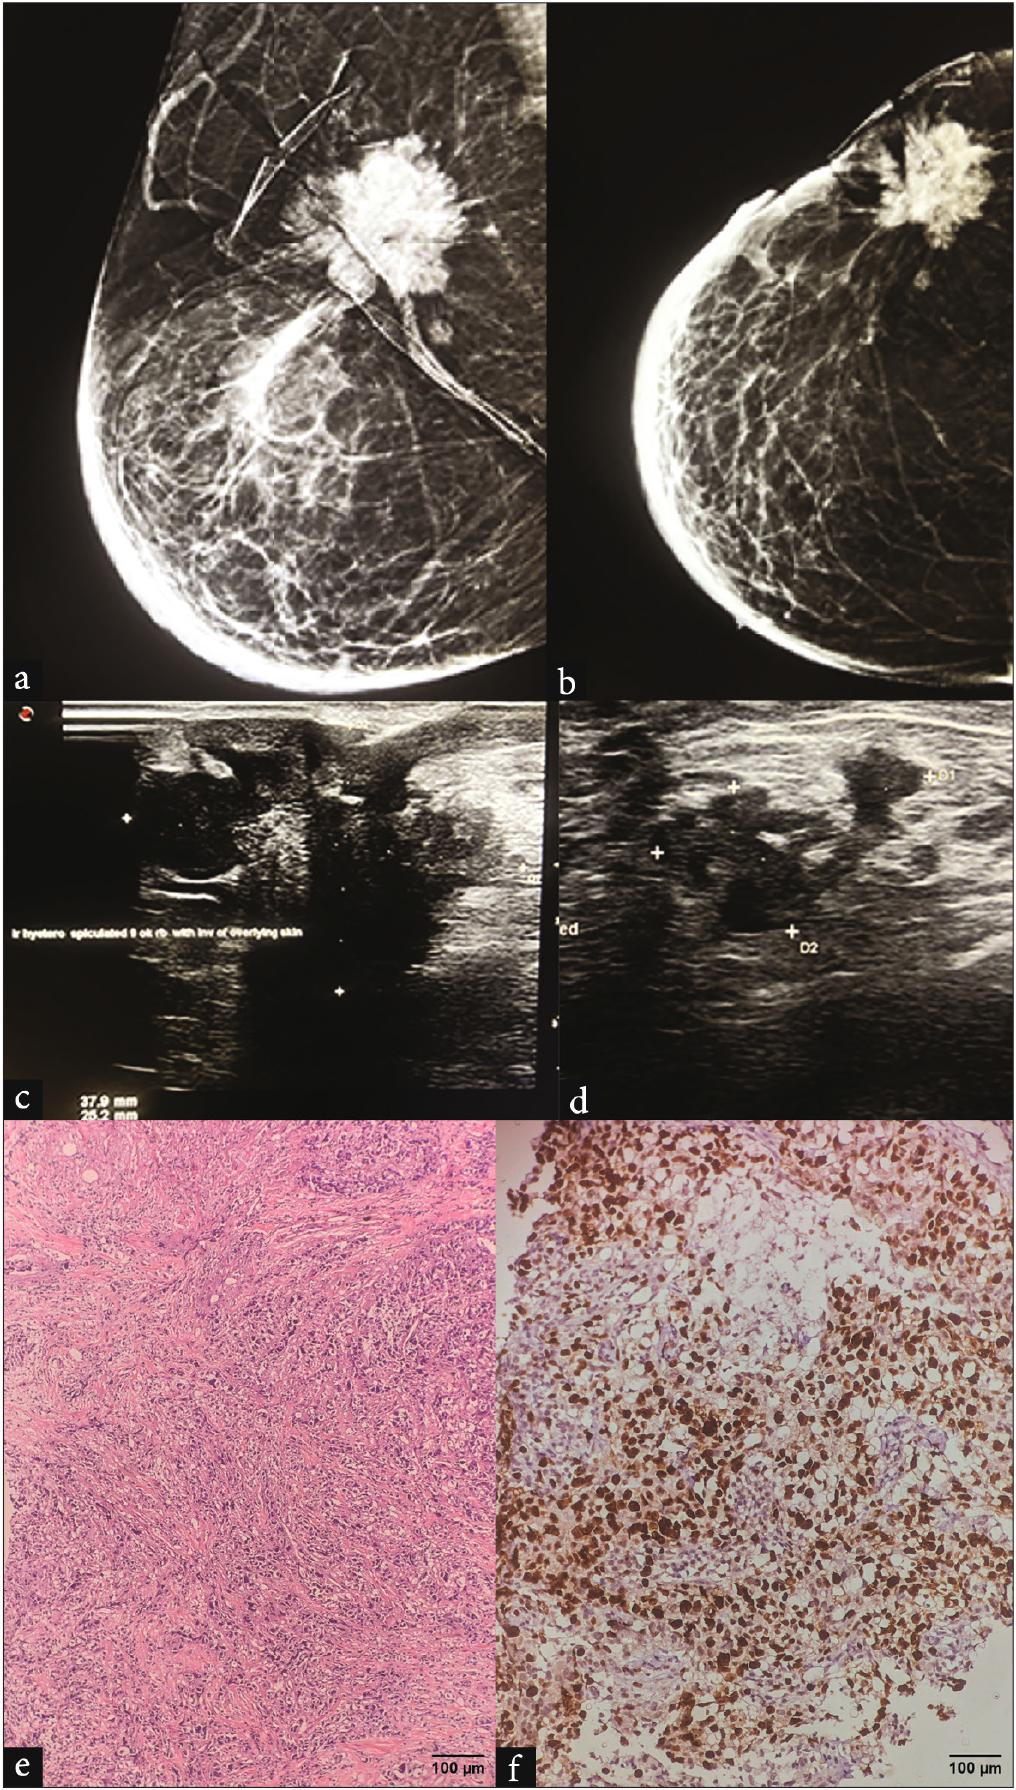

- A 38-year-old female presented with a palpable lump in the right breast in the upper outer quadrant. (a-b) MLO and CC view of mammogram of right breast reveal An irregular high-density mass with spiculated margins and associated skin retraction and invasion. Diffuse skin and trabecular thickening noted secondary to lymphatic obstruction. (c) Corroborative grayscale ultrasound shows an irregular heterogeneous mass with spiculated margins and shadowing. (d) USG of the ipsilateral axilla revealed irregular level I lymph node with extracapsular breach. (e) H&E, 20x: grade 3 invasive breast carcinoma, NST. (f) Ki67 labeling index: 70%–80%, grade 3 IBC, NST. MLO: Mediolateral oblique, CC: Cranio caudal, USG: Ultrasound, H&E: Hematoxylin and eosin, NST: Non specific type.